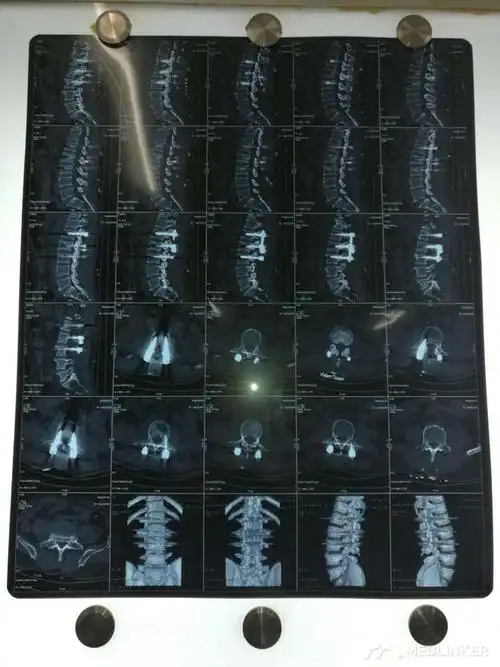

腰椎骨折